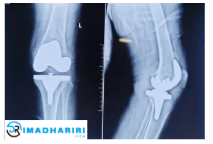

محمي: Knee Surgery جراحة الركبة